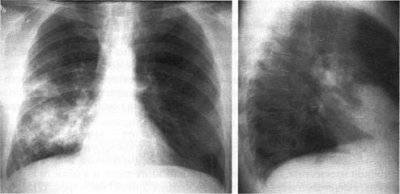

Признаки заболевания

Флюорография позволяет выявить различные патологические изменения в легочной ткани.

Примеры:

| Усиление легочного рисунка | Легочной рисунок представляет собой сплетение кровеносных сосудов. При различных гемодинамических нарушениях он деформируется, становится более плотным. Иногда определяются участки повышенной прозрачности. Патологические изменения выявляются при следующих проблемах:

| Очаговые тени | Характерны для:

Могут быть как очаговыми, так и множественными. Большое значение имеет размер патологического образования. |

| Кальцинаты | Признак инфекционного процесса. |

| Патологические изменения корня легкого | Возможны следующие нарушения:

| Фиброзы | Замещение легочной ткани соединительной – последствие воспаления. | Фиброзно-кавернозный туберкулез |

| Скопление жидкости в плевральной полости | Признак воспаления плевры. |

| Смещение органов грудной клетки | Оценивается положение:

Смещение наблюдается при новообразованиях легких и средостения, сердечной патологии и скоплении жидкости в плевральной полости. |

| Изменения положении диафрагмы | Нередко наблюдается после травм и оперативных вмешательств. | Высокое положение купола диафрагмы |

Регулярное профилактическое обследование помогает выявить туберкулез и многие онкологические заболевания в ранней стадии. Своевременное начало лечения подарит надежду на выздоровление.